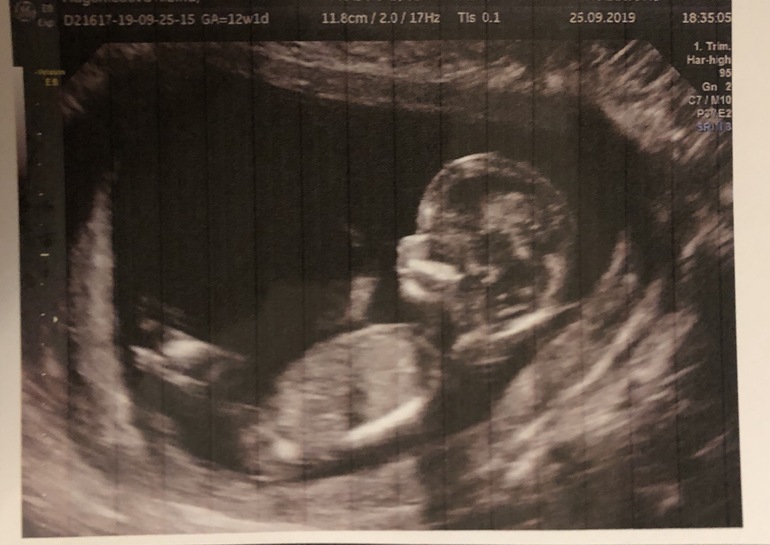

Фото малыша

Результаты: УЗИ, КТГ, доплера, скрининга

Итак ножки мы скрестили)) пол не показали и ждём второго скрининга)) Нутром почему то настроена на мальчика)